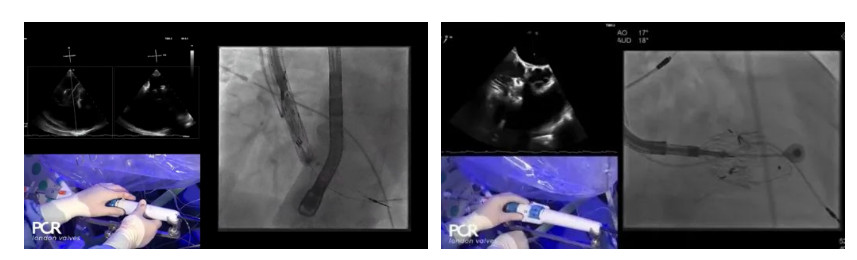

在Thomas Modine教授的線上指導(dǎo)下,德國Mainz中心Ralph Stephan von Bardeleben教授完成了LuX-Valve Plus經(jīng)血管三尖瓣置換系統(tǒng)在其所在中心的首例植入,術(shù)后Stephan教授高度贊揚(yáng)LuX-Valve Plus人工三尖瓣瓣膜“植入過程高度可控,安全有效”。接受治療的是一例82歲的高齡男性患者,術(shù)前NYHAⅢ級,因復(fù)發(fā)心衰入院,有逾5年的慢性房顫病史。這例患者因特殊的解剖結(jié)構(gòu)以及較大的三尖瓣瓣環(huán),有起搏器植入史,被所有其他經(jīng)導(dǎo)管三尖瓣修復(fù)或置換器械的臨床排除在外,因此等了一年半才等到此次LuX-Valve Plus的手術(shù)機(jī)會,實(shí)屬不易。

手術(shù)在全麻狀態(tài)下開展,采用經(jīng)右側(cè)頸靜脈入路的方式將輸送器送入患者心臟內(nèi),在TEE及DSA引導(dǎo)下調(diào)整輸送器頭端角度,使得輸送器與三尖瓣瓣環(huán)平面垂直。在輸送器進(jìn)入右心室后釋放室間隔錨定裝置,而后釋放瓣葉夾持件(2個耳片結(jié)構(gòu))成垂直狀態(tài)。在TEE及DSA確定夾持件固定至三尖瓣葉根部且位于右室側(cè)后釋放人工瓣心房側(cè)盤片。隨后調(diào)整瓣膜同軸性以及室間隔錨定件位置(貼合室間隔),前推藏針管并固定,進(jìn)而釋放室間隔錨定裝置,并再次確認(rèn)瓣膜位置、穩(wěn)定性及同軸性,合攏輸送鞘后撤出輸送器,完成LuX-Valve Plus人工三尖瓣瓣膜的植入。